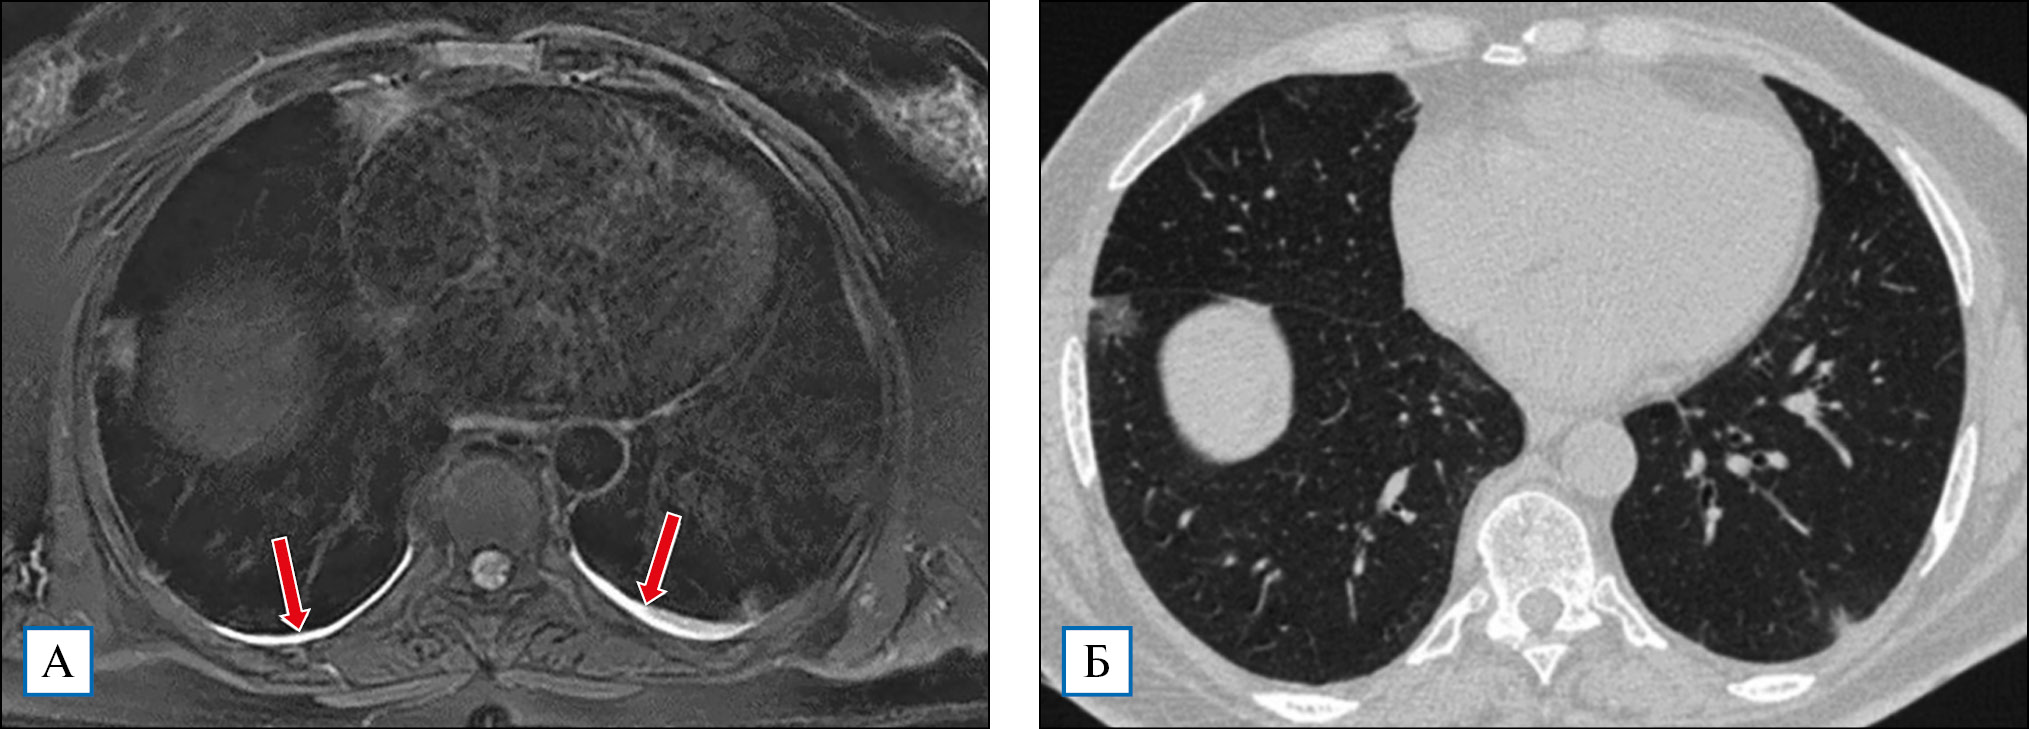

Рис. 4. Т2-ВИ МРТ имеет заметные преимущества в сравнении с КТВР в выявлении небольших объемов жидкости в плевральных полостях. Малый двусторонний гидроторакс у пациентки Б., 69 лет (стадия КТ1), уверенно выявляется на Т2 МРТ (стрелки, А) и практически не отображается на КТВР-срезах (Б)